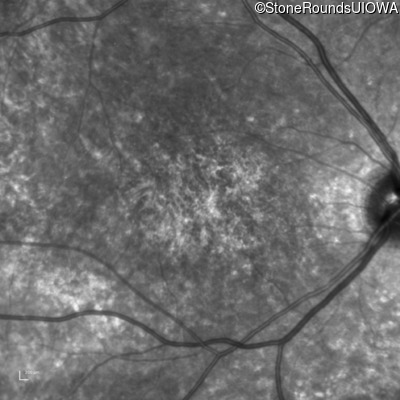

Age at visit: 15 years

OD OS

Age at visit: 16 years

Age at visit: 19 years

Age at visit: 23 years